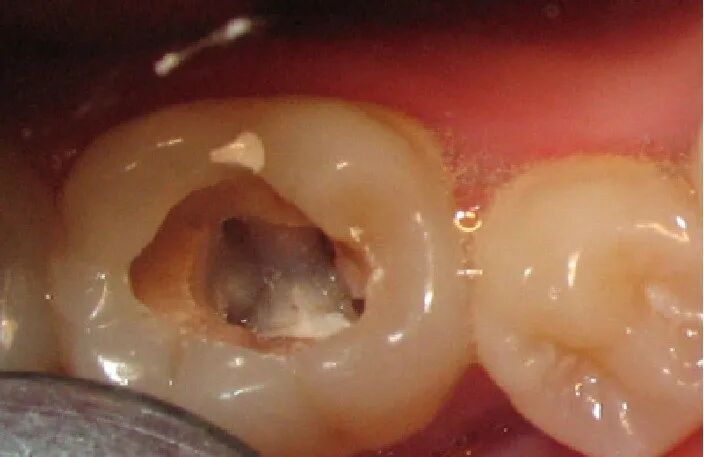

1、自发疼痛史;

2、不可逆性牙髓炎、牙髓坏死、根尖周炎;

3、行冠髓切断后仍然流血不止;

1、常规制备洞形

去除龋坏组织制备洞形,开髓,揭去髓室顶。

2、根管预备

去除髓室顶和根管内的坏死的牙髓,使用根管器械扩挫根管。

活髓:局麻下拔髓或失活后拔髓;

死髓:去除髓室和根管的坏死牙髓。